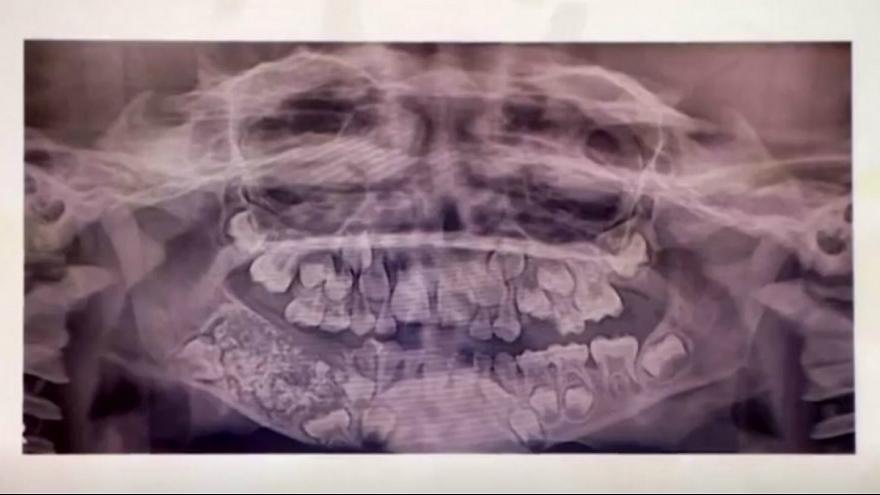

در شرایطی که بسیاری از افراد برای ترمیم یک دندان خود مشکل دارند کودک هفت ساله هندی 526 دندان اضافی داشت. این کودک پس از شکایت از تورم و درد در فک ، توسط والدینش به دانشکده دندانپزشکی ساوتتا و بیمارستان در تامیل نادو برده شد.

هنگامی که جراحان بالاخره توانستند نگاهی به دهان کودک بیندازند، ضایعه بزرگی را به همراه تعدادی ساختار سخت در فک پایین او کشف کردند.در بازرسی بیشتر ، توده ای مانند کیسه کشف شد که پزشکان به طور کامل آن را حذف کردند.پس از اسکن و بررسی برای بررسی اینکه آیا سرطانی است یا خیر آنها موادی داخل آن کشف کردند. هنگامی که آن را باز کردند، آنها متوجه شدند که پر از دندان است و در نتیجه شوکه شدند.

حدود پنج ساعت طول کشید تا هر یک از دندانهای اضافی توسط پزشکان شمارش شود. پروفسور سنتیلناتان ، یک جراح دهان و فک و صورت در بیمارستان ، در این این خصوص گفت: "رشد تومور مانند مانع از رشد دائمی دندانهای این گسر شده بود و درد نیز به همین دلیل بود. وزن توده دهانی این کودک 200 گرم بود. ما بیهوشی عمومی به بیمار دادیم وکل جراحی را یک ساعت و نیمه به پایان بردیم. "